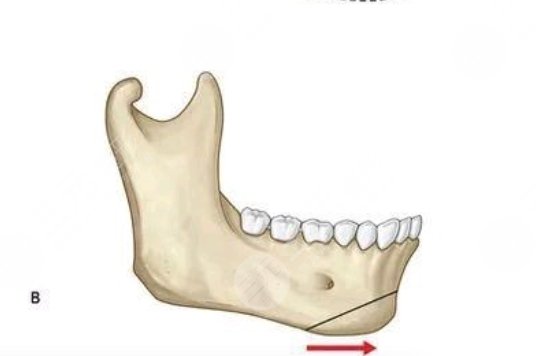

①颏成型手术:通过专业化的形式塑造出更加精致且立体的下巴形态,解决下颌骨发育不足等问题,实现整个面部形态的焕然一新。

④下颌角截骨:采用长曲线的医疗技术方法,切除多余的骨骼组织,这样可以打造出精致又好看的脸型。

Answer:通过个性化的设计、修整、调整之后加以固定,从而改变下巴的形态,解决后缩以及前移的问题。